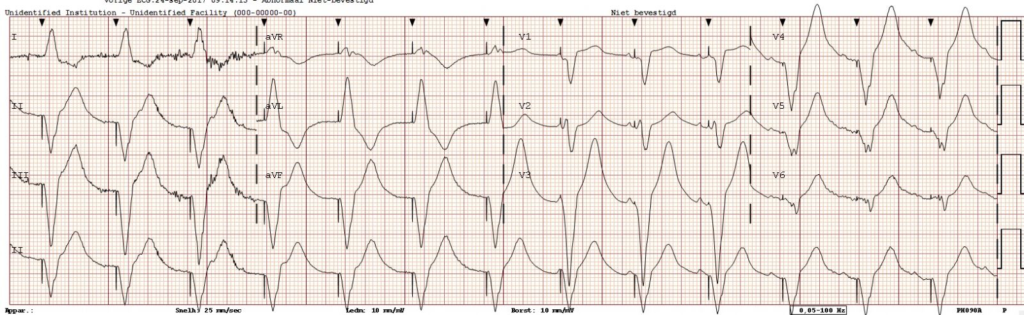

Figuur 3: Elektrocardiogram met atriale- en ventriculaire stimulatie (DDD-pacemakerritme)